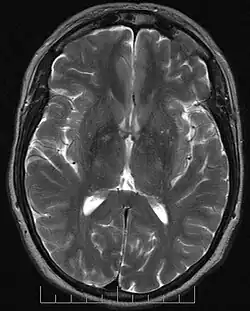

En neurosciences, la tractographie est une méthode utilisée pour mettre en évidence les voies neuronales[ref 1]. Elle utilise une technique spéciale d’IRM avec une technique particulière du tenseur de diffusion. Les résultats sont présentés sous forme d'images deux et trois dimensions.

Les séquences d’IRM utilisées en tractographie étudient la symétrie de la diffusion de l’eau dans le cerveau. Les faisceaux de fibres provoquent une diffusion asymétrique de l’eau dans un tenseur. Son axe principal est parallèle à la direction des fibres. Cette asymétrie est appelée anisotropie. Il existe un lien direct entre le nombre de fibres et le degré d’anisotropie.

La tractographie est réalisée grâce à l'imagerie du tenseur de diffusion. L'IRM de diffusion, introduite, notamment pour son potentiel en neuroimagerie par Denis Le Bihan dès 1985 [1],[2] permet d'obtenir des images de la diffusion moléculaire, notamment de l'eau. Une évolution de l'IRM de diffusion, l'imagerie du Tenseur de Diffusion [3],[4], permet de caractériser la diffusion moléculaire dans les 3 dimensions de l'espace. La diffusion libre se produit de manière homogène dans toutes les directions (mouvement brownien). On l'appelle diffusion isotropique. Si l'eau diffuse dans un milieu avec des barrières, la diffusion sera privilégiée dans certaines directions. On l'appelle diffusion anisotropique. Dans un tel cas, la mobilité des molécules à partir de leur origine de départ a une forme différente d'une sphère. La forme peut-être ellipsoïde. Cette technique est appelée technique d'imagerie du tenseur de diffusion. Les barrières peuvent être de multiples types : membranes cellulaires, axones, gaines de myéline, etc. Dans le cerveau, la principale barrière est la gaine de myéline. Des faisceaux d'axones forment une barrière empêchant une diffusion perpendiculaire et un chemin pour la diffusion parallèle le long de l'orientation des fibres. On s'attend à ce que la diffusion anisotropique soit augmentée dans les zones d'ordre axonal maximum. Dans certaines pathologies, la structure des axones est perturbée comme dans les traumatismes, les tumeurs ou les inflammations. L'anisotropie, par destruction ou désorganisation des barrières est donc augmentée. L'anisotropie est mesurée de différentes manières. L'une d'entre elles consiste à évaluer un ratio appelé anisotropie fractionnelle (AF). Une anisotropie de 0 correspond à une sphère parfaite alors qu'un ratio à 1 correspond à une diffusion linéaire idéale. Des trajets bien délimitables ont une AF plus grande que 0,20. Peu de régions ont une AF de plus de 0,80. La valeur donne une information sur la non-sphéricité de la diffusion mais ne donne pas d'information sur sa direction. Chaque anisotropie est liée à une orientation sur un axe prédominant (direction prédominate de la diffusion) Des programmes informatiques sont capables d'extraire cette information directionnelle. Cette information additionnelle est difficile à représenter sur des images en 2D en échelles de gris. Pour surmonter ce problème, un code coloré est ajouté. Des couleurs basiques informent sur l'orientation des fibres dans un système avec des coordonnées dans les 3 dimensions. On parle de plan anisotropique. Conventions de couleurs :